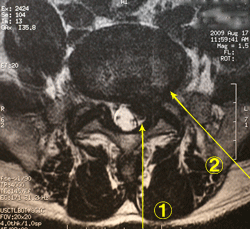

a)は最も古典的な方法です。右図の@のように侵入し、直視下に

ヘルニアを取り除きます。慣れれば30分位で終了し、翌日には歩

けます。安静期間や入院期間は絶対的なものではなく、施設によ

って異なります。 ⇒参考

c)は、右図のAの経路で椎間板内に直径約4mmの管を挿入して髄核を取り除く方法です。 局所麻酔で治療可能ですが、脱出したヘルニアを直接取り除くわけではないので、 効果の得られる症例が限られます(年齢が若いこと、ヘルニアが完全脱出していないことなど)。

d)はc)と同様なことをレーザーを使って行うものです。右図Aの経路から機器を挿入し、 レーザーを椎間板内に照射して髄核を蒸発させる方法です。これによって椎間板内の圧力が減少し、 神経の圧迫が軽減されるというものです。 これも、脱出したヘルニアを直接取り除くわけではないので、 効果のある症例は限られます。